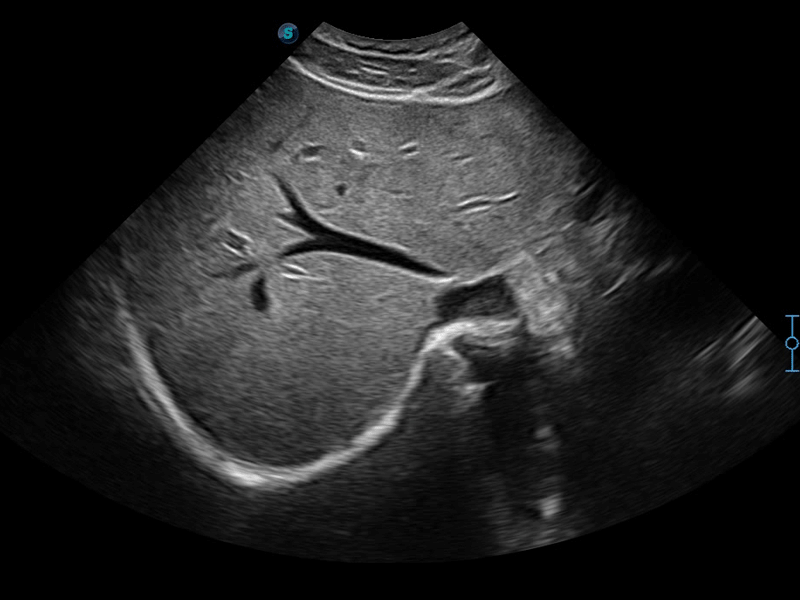

扩展成像技术

凸阵、线阵和相控阵探头进行实时扫描时,开启扩展成像模式,可以扩展超声图像视野,以便更完整地查看大的病灶或组织器官的解剖结构。